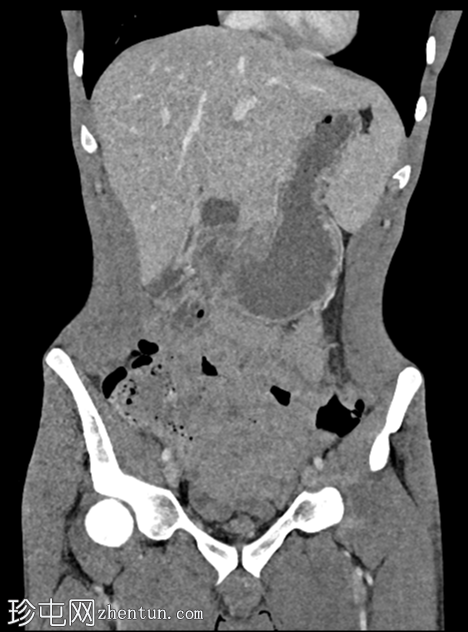

轴位增强CT(门静脉期)

增强CT扫描显示双侧肾积水、输尿管积水伴输尿管黏膜弥漫性强化,以及膀胱容量缩小伴黏膜强化。未见尿路结石或肾周脂肪浸润/积聚。

考虑到患者有氯胺酮滥用史,CT扫描结果符合氯胺酮诱发性尿路病变的诊断。